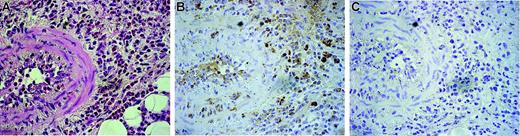

As shown in Figure 1, peripheral eosinophils from CSS patients expressed endogenous DDR1. The DDR1-positive percentage of CSS patients was significantly higher than that of asthma patients and healthy volunteers (Figure 1A-B). The total amount of DDR1 protein was also higher per 1 × 107 eosinophils in CSS patients, and the proportion of cells expressing the DDR1b isoform was also considerably higher in the eosinophils of these patients (Figure 1C-D). There was no significant difference in the concentrations of β1 integrin and another collagen receptor among the 3 groups. Immunohistochemical analysis revealed that the eosinophil staining in the blood vessels and in the wall of the blood vessels was positive for DDR1. Tissue-infiltrating eosinophils also stained positive for DDR1 (Figure 2).

Immunohistochemical analysis of DDR1 expression in the biopsied tissue of a CSS patient. Original magnification, × 350. (A) Hematoxylin-eosin staining. (B) Stained with the DDR1 antibody. (C) Negative control for the DDR1 antibody. Cells were stained with hematoxylin. Images were captured with an Olympus U-PMTVC microscope (Olympus, Tokyo, Japan) with a UPlan Apo 20×/0.80 NA objective lens, and an Olympus DP11-N. Images were captured with Adobe Photoshop 7.0 (Adobe Systems, San Jose, CA).